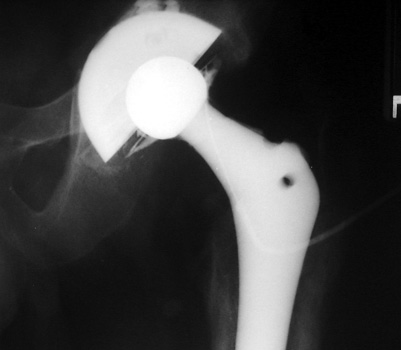

Normal arthrogram